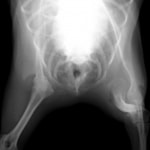

左後肢の完全挙上を主訴に来院されました。触診にて近位足根関節の過伸展を、レントゲン検査にて左足根関節周囲の軟部組織の腫脹、ストレス撮影によって距骨・踵骨と第4足根骨・中心足根骨間の脱臼および過伸展を認めました。

術前正面像左関節の腫れ

左足根関節の軟部組織が腫脹しています。

術前正面像